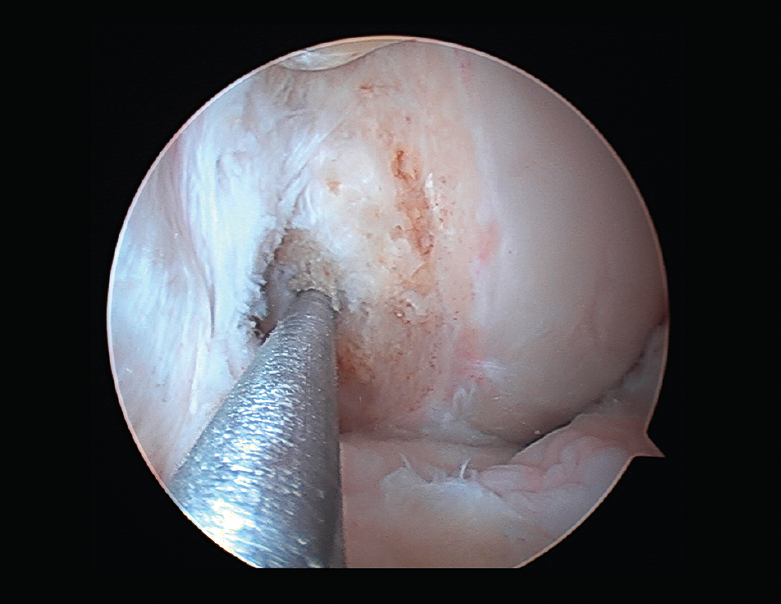

Las principales causas secundarias a errores técnicos son la malposición de la plastia y el tensado excesivo. La radiografía permite ver la localización de los túneles e implantes, así como la RM visualiza las partes blandas implicadas, pudiendo identificar posibles pinzamientos de la plastia –escotadura intercondílea, síndrome del cíclope (Figura 9), síndrome de la contractura infrapatelar(22)(Figura 10)–.

Figura 9. Cíclope, tejido fibroso interpuesto en la cara anterior de la plastia y que produce pinzamiento de la misma en extensión de rodilla.